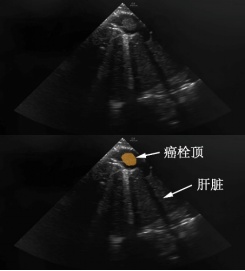

术中经食道超声影像

麻醉科副主任医师沈子珒通过超声探查发现分离层面未到癌栓顶端。在胸外科陈中元主任医师、陈学瑜副主任医师指导下,潘隽玮切开膈肌,分离至癌栓顶端。普外科医师又分离出第一肝门。血管准备完毕后,血管外科团队置入介入球囊,跨越癌栓并在右心房内展开。